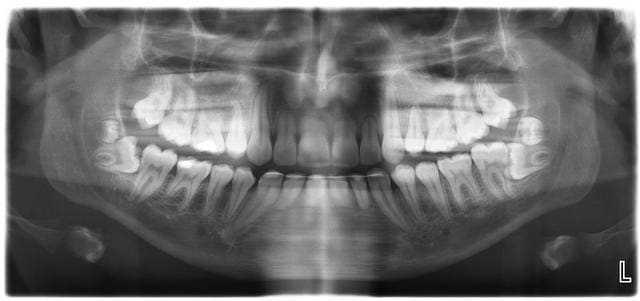

Patient adresse pour extraire 48-38. Seules des btw sont dans le dossier.

Petite pano pre op :0))